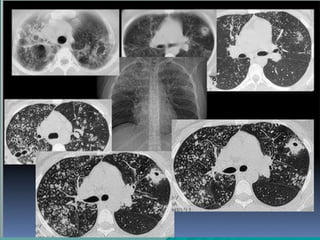

TECNICA DE BAJA DOSIS YTECNICA DE BAJA DOSIS Y

ALTA RESOLUCIONALTA RESOLUCION

Se realizan cortes finos de 1 mm de grosor aSe realizan cortes finos de 1 mm de grosor a

intervalos de 10 mm para el estudio inicial y cortesintervalos de 10 mm para el estudio inicial y cortes

de 1 mm a intervalo de 20 mm para el seguimientode 1 mm a intervalo de 20 mm para el seguimiento

de la patología pulmonar crónicade la patología pulmonar crónica

En el caso de los prematuros, la secuencia es deEn el caso de los prematuros, la secuencia es de

cortes de 1 mm cada 5 mm debido al pequeñocortes de 1 mm cada 5 mm debido al pequeño

tamaño del tórax.tamaño del tórax.

Neumol Pediatr 2015; 10 (2): 67 - 71Neumol Pediatr 2015; 10 (2): 67 - 71